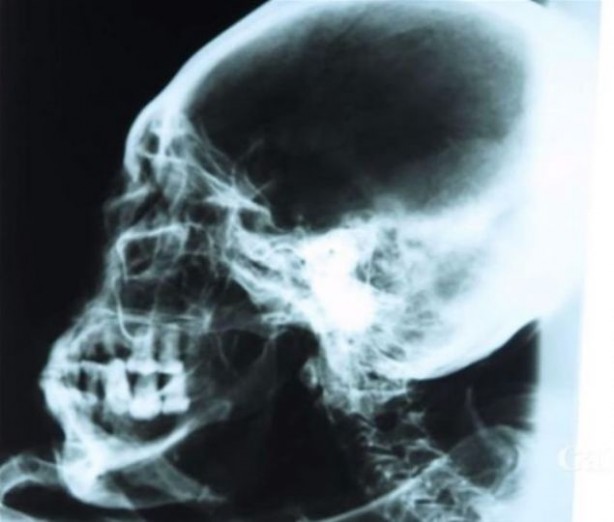

İnce uzun bir kafatası ile üçer parmaktan oluşan el ve ayakları olduğu belirlenen mumyanın, farklı bir canlı türü ya da dünya dışı bir varlık olup olmadığı araştırılıyor.

Eski Mısır’da mumyalama işlemi farklı statüdeki ölen kişiye göre, farklı şekilde uygulandı.Firavunlar mumyalanırken, iç organları özenle çıkartıldı, beyni dahi yerinden itinayla sökülüp alındı.

En önemli kısım ise o dönem için ölen firavunun burnuydu. Firavunun burnunun zarar görmemesi için özenle çalışırdı ustalar.

Ölümden sonraki yaşama inanan Eski Mısırlılar, ölen kişinin ruhunun geri döneceğine ve döndüğü zamanda eski bedeninin hazır olarak onu beklemesi gerektiğine inandı.